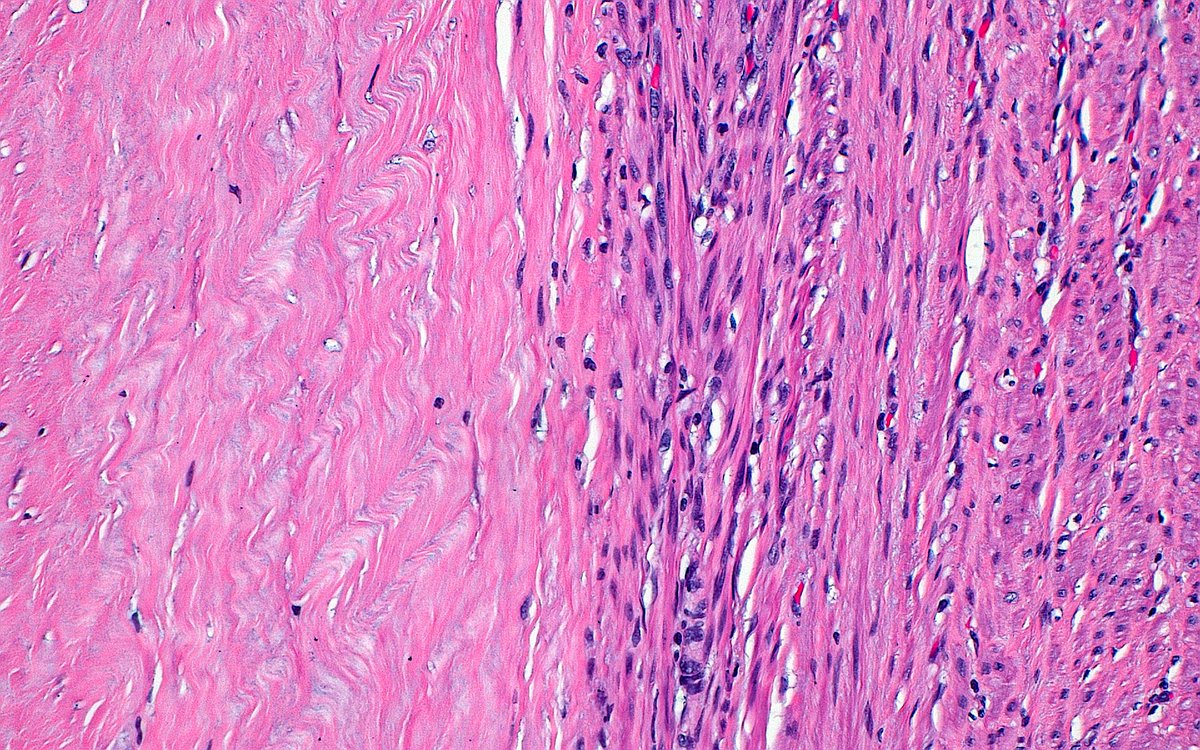

🔬 Leiomyoma with Hyaline Change ~ Collagen fibers (left half of image) next to smooth muscle cells (right half) that transitioned to an area of ischemic type necrosis (outside field of image) ~ #GYNpath #Pathology #Histology

ziad_zaatari's tweet image. 🔬 Leiomyoma with Hyaline Change ~ Collagen fibers (left half of image) next to smooth muscle cells (right half) that transitioned to an area of ischemic type necrosis (outside field of image) ~ #GYNpath #Pathology #Histology